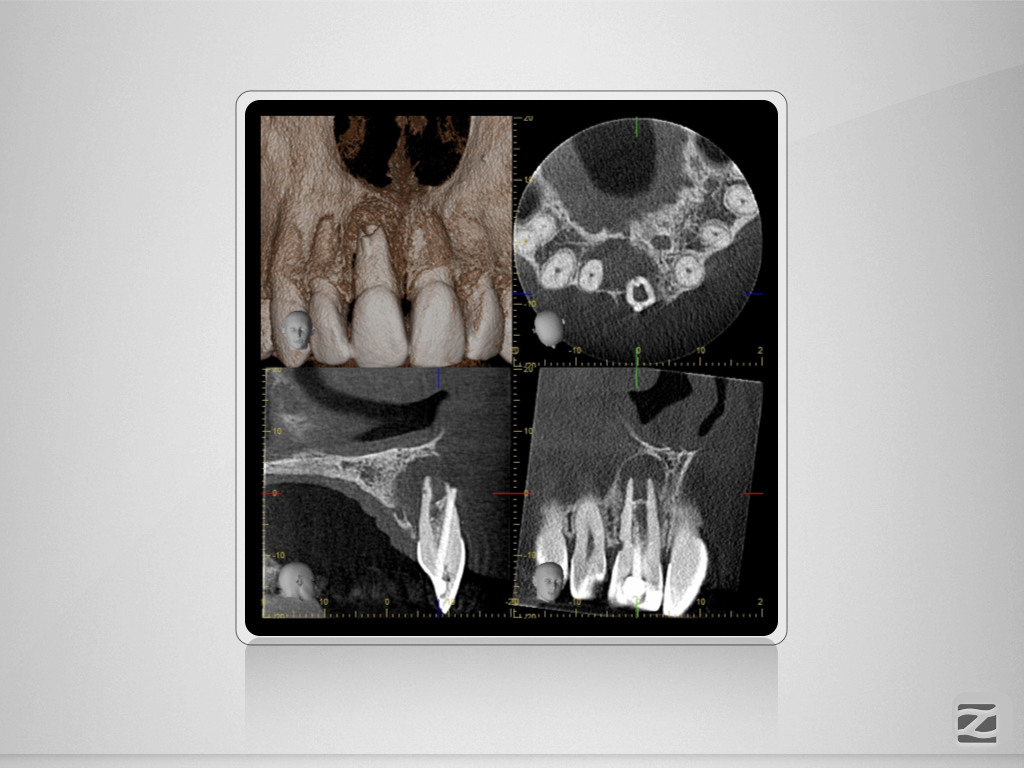

Traumabehandlung – State of the Unart